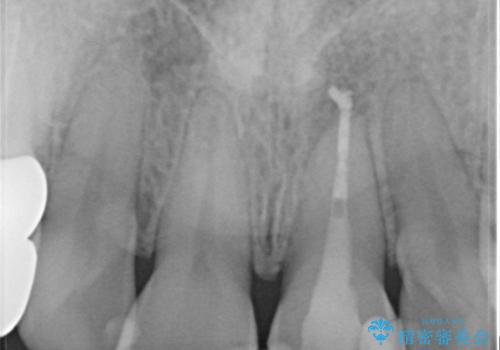

捻れている歯は、神経が露出する可能性があり、その場合には根管治療が必要となります。

神経が露出しないよう慎重に行った結果、神経を保存することができました。処置後に多少の痛みが生じましたが、その後は良好な状態が続いています。